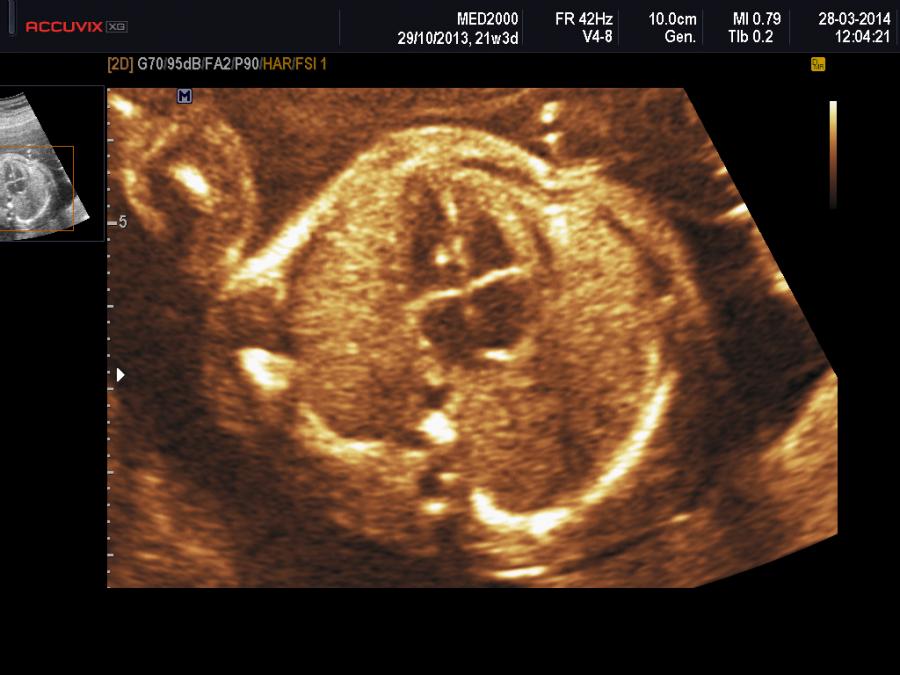

La Golf Ball è una piccola struttura ad ecogenicità comparabile con quella dell'osso fetale tipicamente presente all'interno dei ventricoli nella regione del muscolo papillare o delle corde tendinee che si muove in sincronia con la valvola mitrale o tricuspide ma non interessa la parete ventricolare (Wax JR et al., 2000; Carriço A et al., 2004; Arda S et al, 2007;  Lorente AMR et al, 2017). Per ridurre i falsi positivi legati al fatto che i muscoli papillari sono spesso visibili come punti ecogenici è utile ridurre il gain per assicurarsi che il FEI non svanisca prima  dell'ecogenicità delle costole (Bethune M. et al., 2007).

Ecograficamente  si osserva in sezione quattro camere apicale (100%) come una piccola formazione ecogena di diametro variabile da 1 a 4 mm. (Wax JR et al., 2000;  Arda S et al, 2007 ).  E' più frequente nel ventricolo sinistro (92%), meno frequente nel ventricolo destro (4%) o bilateralmente (4%)( Wei M et al., 2018); rare sono la localizzazione intra-atriale o come foci diffusi (Wax JR et al., 2000;  Arda S et al, 2007; ).